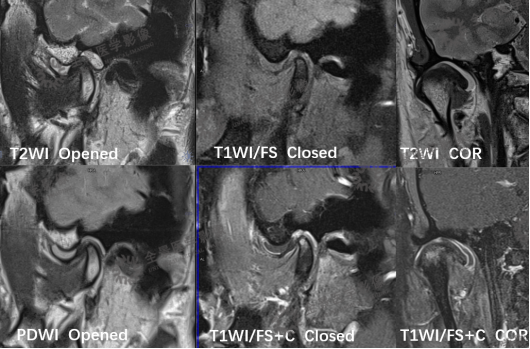

颞颌磁共振检查

MRI:可清楚、全面地反映关节结构及附件组织的变化。MR 动态电影能够很好地显示关节盘、髁状突的运动情况